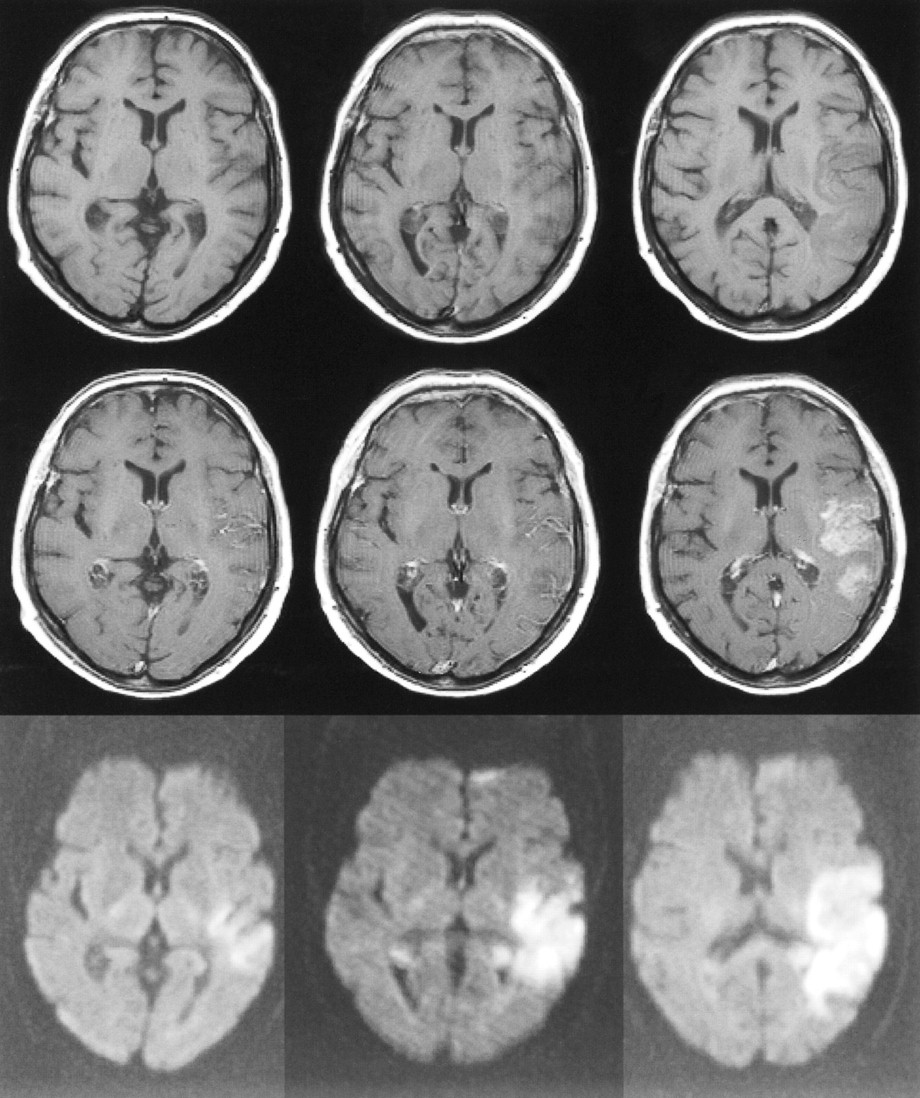

73-year-old man with left hemiparesis. The first MR examination (left column) was performed 23 hours after the onset of symptoms, the second MR examination (middle column) was performed on the second day, and the third MR examination (right column) 1 week after stroke.

Top row, Unenhanced T1-weighted images (600/14/1) are normal on the first and second days, but at 1 week, slightly increased signal intensity is observed in the cortex due to microhemorrhage or cortical laminar necrosis.

Middle row, Contrast-enhanced T1-weighted images (600/14/1) show intravascular enhancement over the infarct on the first day. Mild cortical enhancement is detected on the second day, progressing to intensive cortical enhancement at 1 week.

Bottom row, Diffusion-weighted trace images (4000/103/1, in raw image acquisition) show the extent of infarcted tissue as areas of increased signal intensity in the territory of the right middle cerebral artery.